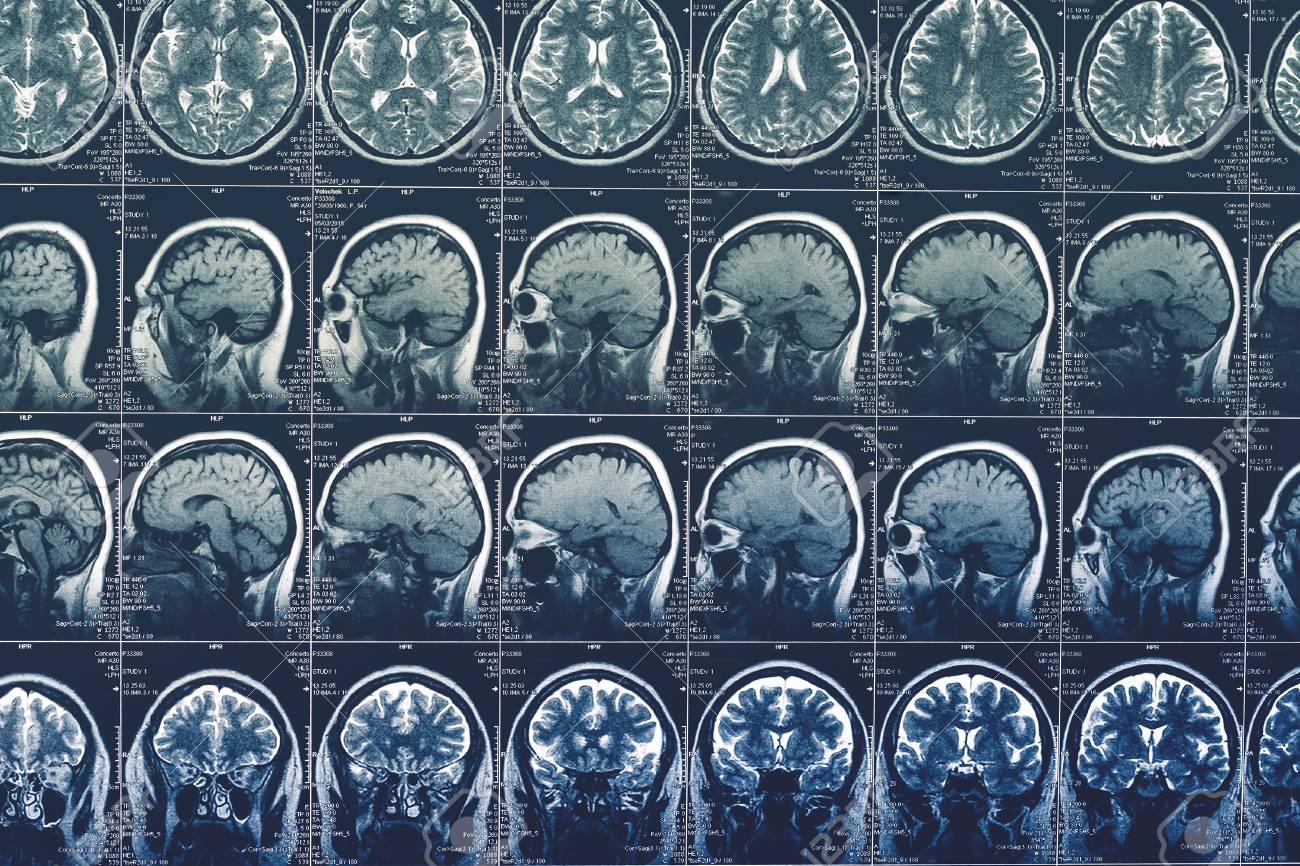

The images be scan